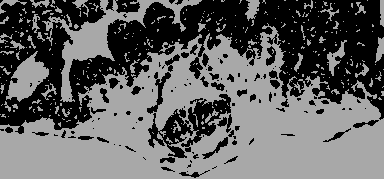

At the beginning of the second week the blastocyst has submerged in the endometrium During implantation the trophoblast develops into the syncytiotrophoblast and the cytotrophoblast which form finally the placenta

The embryoblast forms the epiblast while the trophoblast gives rise to the hypoblast The hypoblast forms the tissue of the primary yolk sac. The epiblast forms the three germ layers.